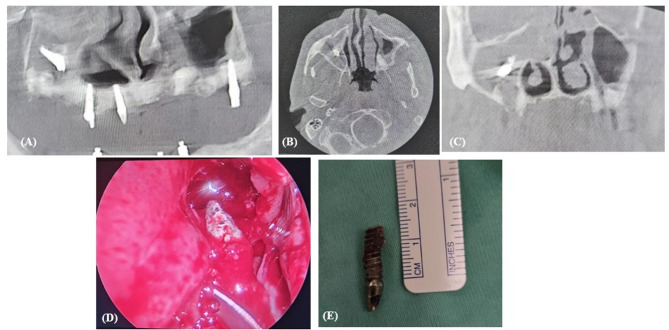

Purpose: This study aims to investigate the potential complication of implant displacement into the maxillary sinus, exploring its etiology and various management strategies, while proposing a systematic approach for clinicians to effectively address this evolving complication.

Materials and methods: This retrospective multi-center cohort study evaluated patients with dental implant migration into the maxillary sinus treated between 2010 and 2023 at two Israeli medical centers. Data included demographics, symptoms, clinical findings, and treatment modalities.

Results: 32 patients (mean age: 62.3 years) were analyzed, with a notable incidence of sinusitis and oroantral fistulas. 91% required surgical intervention, predominantly Functional Endoscopic Sinus Surgery (63%). The majority of displacements occurred during the implantation process, often correlating with clinical symptoms.

Conclusion: As shown in our study, displacement of implants into maxillary sinus, often leads to sinusitis and oroantral fistula. A proposed treatment algorithm emphasizes surgical intervention, particularly Functional Endoscopic Sinus Surgery, based on symptoms and clinical signs.